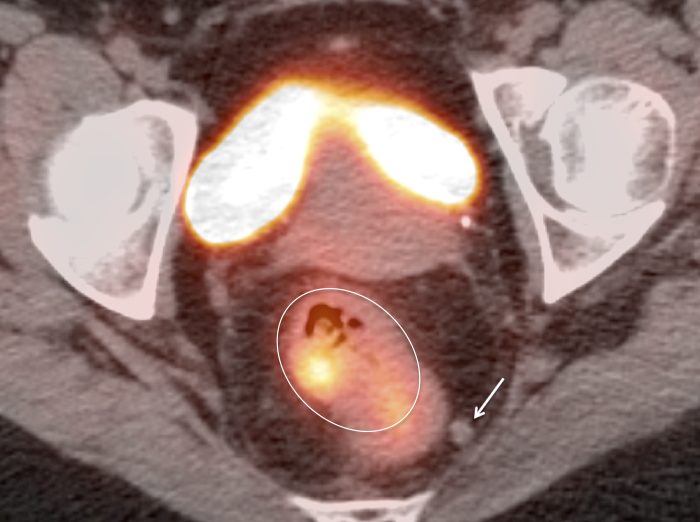

• Hemorrhoids are often intensely avid in the ano-rectal region (and are usually not visible on the CT images). Be certain that uptake does not lie more superiorly in the rectum. Additionally, carefully assess for an accompanying soft tissue density to exclude an anal cancer.

• Beware the small rectal cancer!  As the ano-rectal region frequently demonstrates intense physiologic uptake, it is very easy to overlook a rectal malignancy, especially if it is an incidental finding.  To avoid this error, always evaluate the rectum carefully on the sagittal whole body images.  It is shocking to see how readily apparent a rectal cancer can be on these images, yet so easily overlooked in the axial plane.